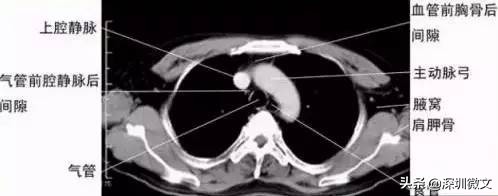

【CT:扫描更具立体感,分辨率更高】

CT正是在这样的医学背景下被研发。CT根本的检查和成像原理与X光相同,但二者最根本的区别在于,X光是将人体的一个或者多个器官投射到同一个平面上进行成像;CT是将人体的一个器官或者多个器官进行一层一层的扫描。

要解释这一点首先还是让我们从“CT”这个名称入手。“CT”的中文全称为“电子计算机断层扫描”。这个所谓的“断层扫描”可以这样理解,在人体的患病部位截取一个长方体,然后再把这个长方体依据不同的层厚与层距分为若干个小长方体进行分别扫描。

这项技术相比X光的突破在哪里呢?X光把前后重叠的肌肉、骨骼、器官全部投射到同一个平面上成像,这就涉及到相互遮挡等问题。这就像你要看一个人的背影,可只有一张正面的照片一样。所以X光的拍摄当中,有患者经常碰到医生要求从不同角度拍摄。

从X光到CT的突破和进步,我们可以广义的理解为:医生从一个长方形到从一个长方体看病变区域的突破。

由于CT的密度分辨率高,所以软策划、骨与关节都能显得很清楚。除了分辨率更高之外,CT机的又一项重大突破,是可以将各个部位对于X光吸收的差异直接量化。所谓的CT值就是对差异的量化,医生对于病变的判断因此更加准确。